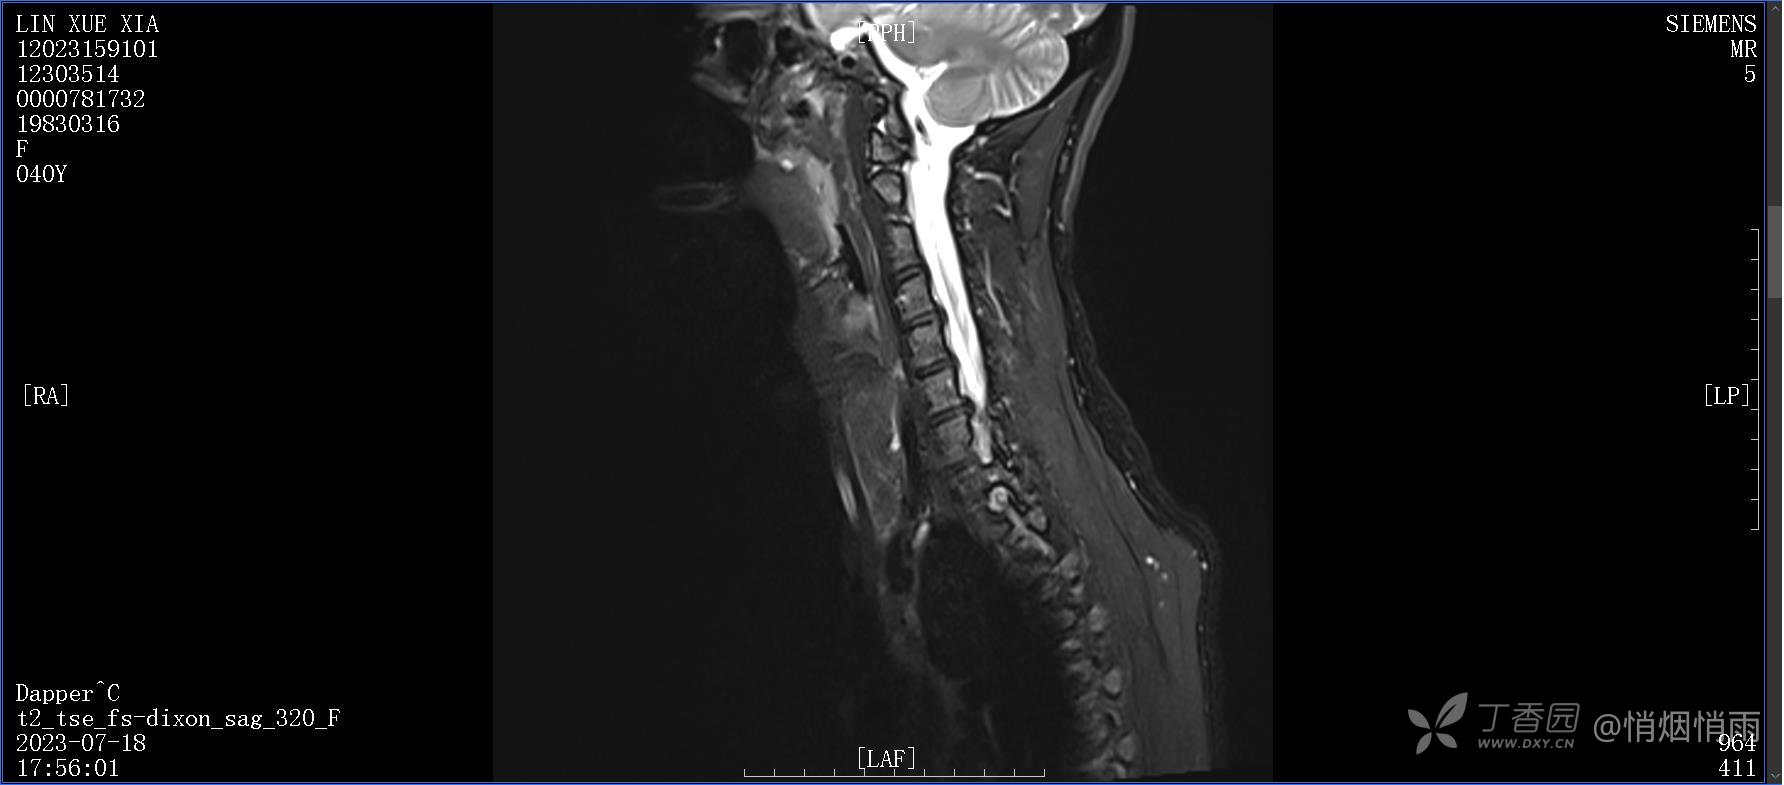

NeurothinkerZ 推荐患者女性,40岁,因右肩背部疼痛班活动受限4日余入院(2023-07-17)。

病史:入院前4天无明显诱因突然感右肩背疼痛伴随活动受限,自行口服依托考昔、艾瑞昔布等药物治疗,院外应用肩关节局部手法按摩等,均无明显改善。外院门诊诊为颈椎病。自诉既往多次“胸椎小关节紊乱”于当地诊所行手法按摩,治疗后好转,否认慢性疾病病史、外伤史、手术史,诉青霉素过敏,无其他药物食物过敏史,否认吸烟史、饮酒史,月经正常,经量正常。

查体:右肩关节局部轻度肿胀,肩胛区压痛明显,痛处不固定,肩关节痛性活动受限,jobe test(+),lift -off test(+),中指、环指感觉较余指减退,余肢端感觉及血运情况可。

此患者行仰头抬下颌、低头收下颌以及将头转向患侧时疼痛明显,俯卧位时疼痛明显,仰卧状态起身时亦可感到疼痛,痛时剧烈。

目前的诊断,暂时依据辅助检查诊为肩袖损伤,但是患者疼痛的性质和特点,却不是单纯的肩袖损伤所致。考虑过胸廓出口综合征,但是该疾病会出现肩胛区的疼痛吗?(由于考虑到费用的问题,没再进行下一步的检查)带状疱疹会有如此的症状吗?